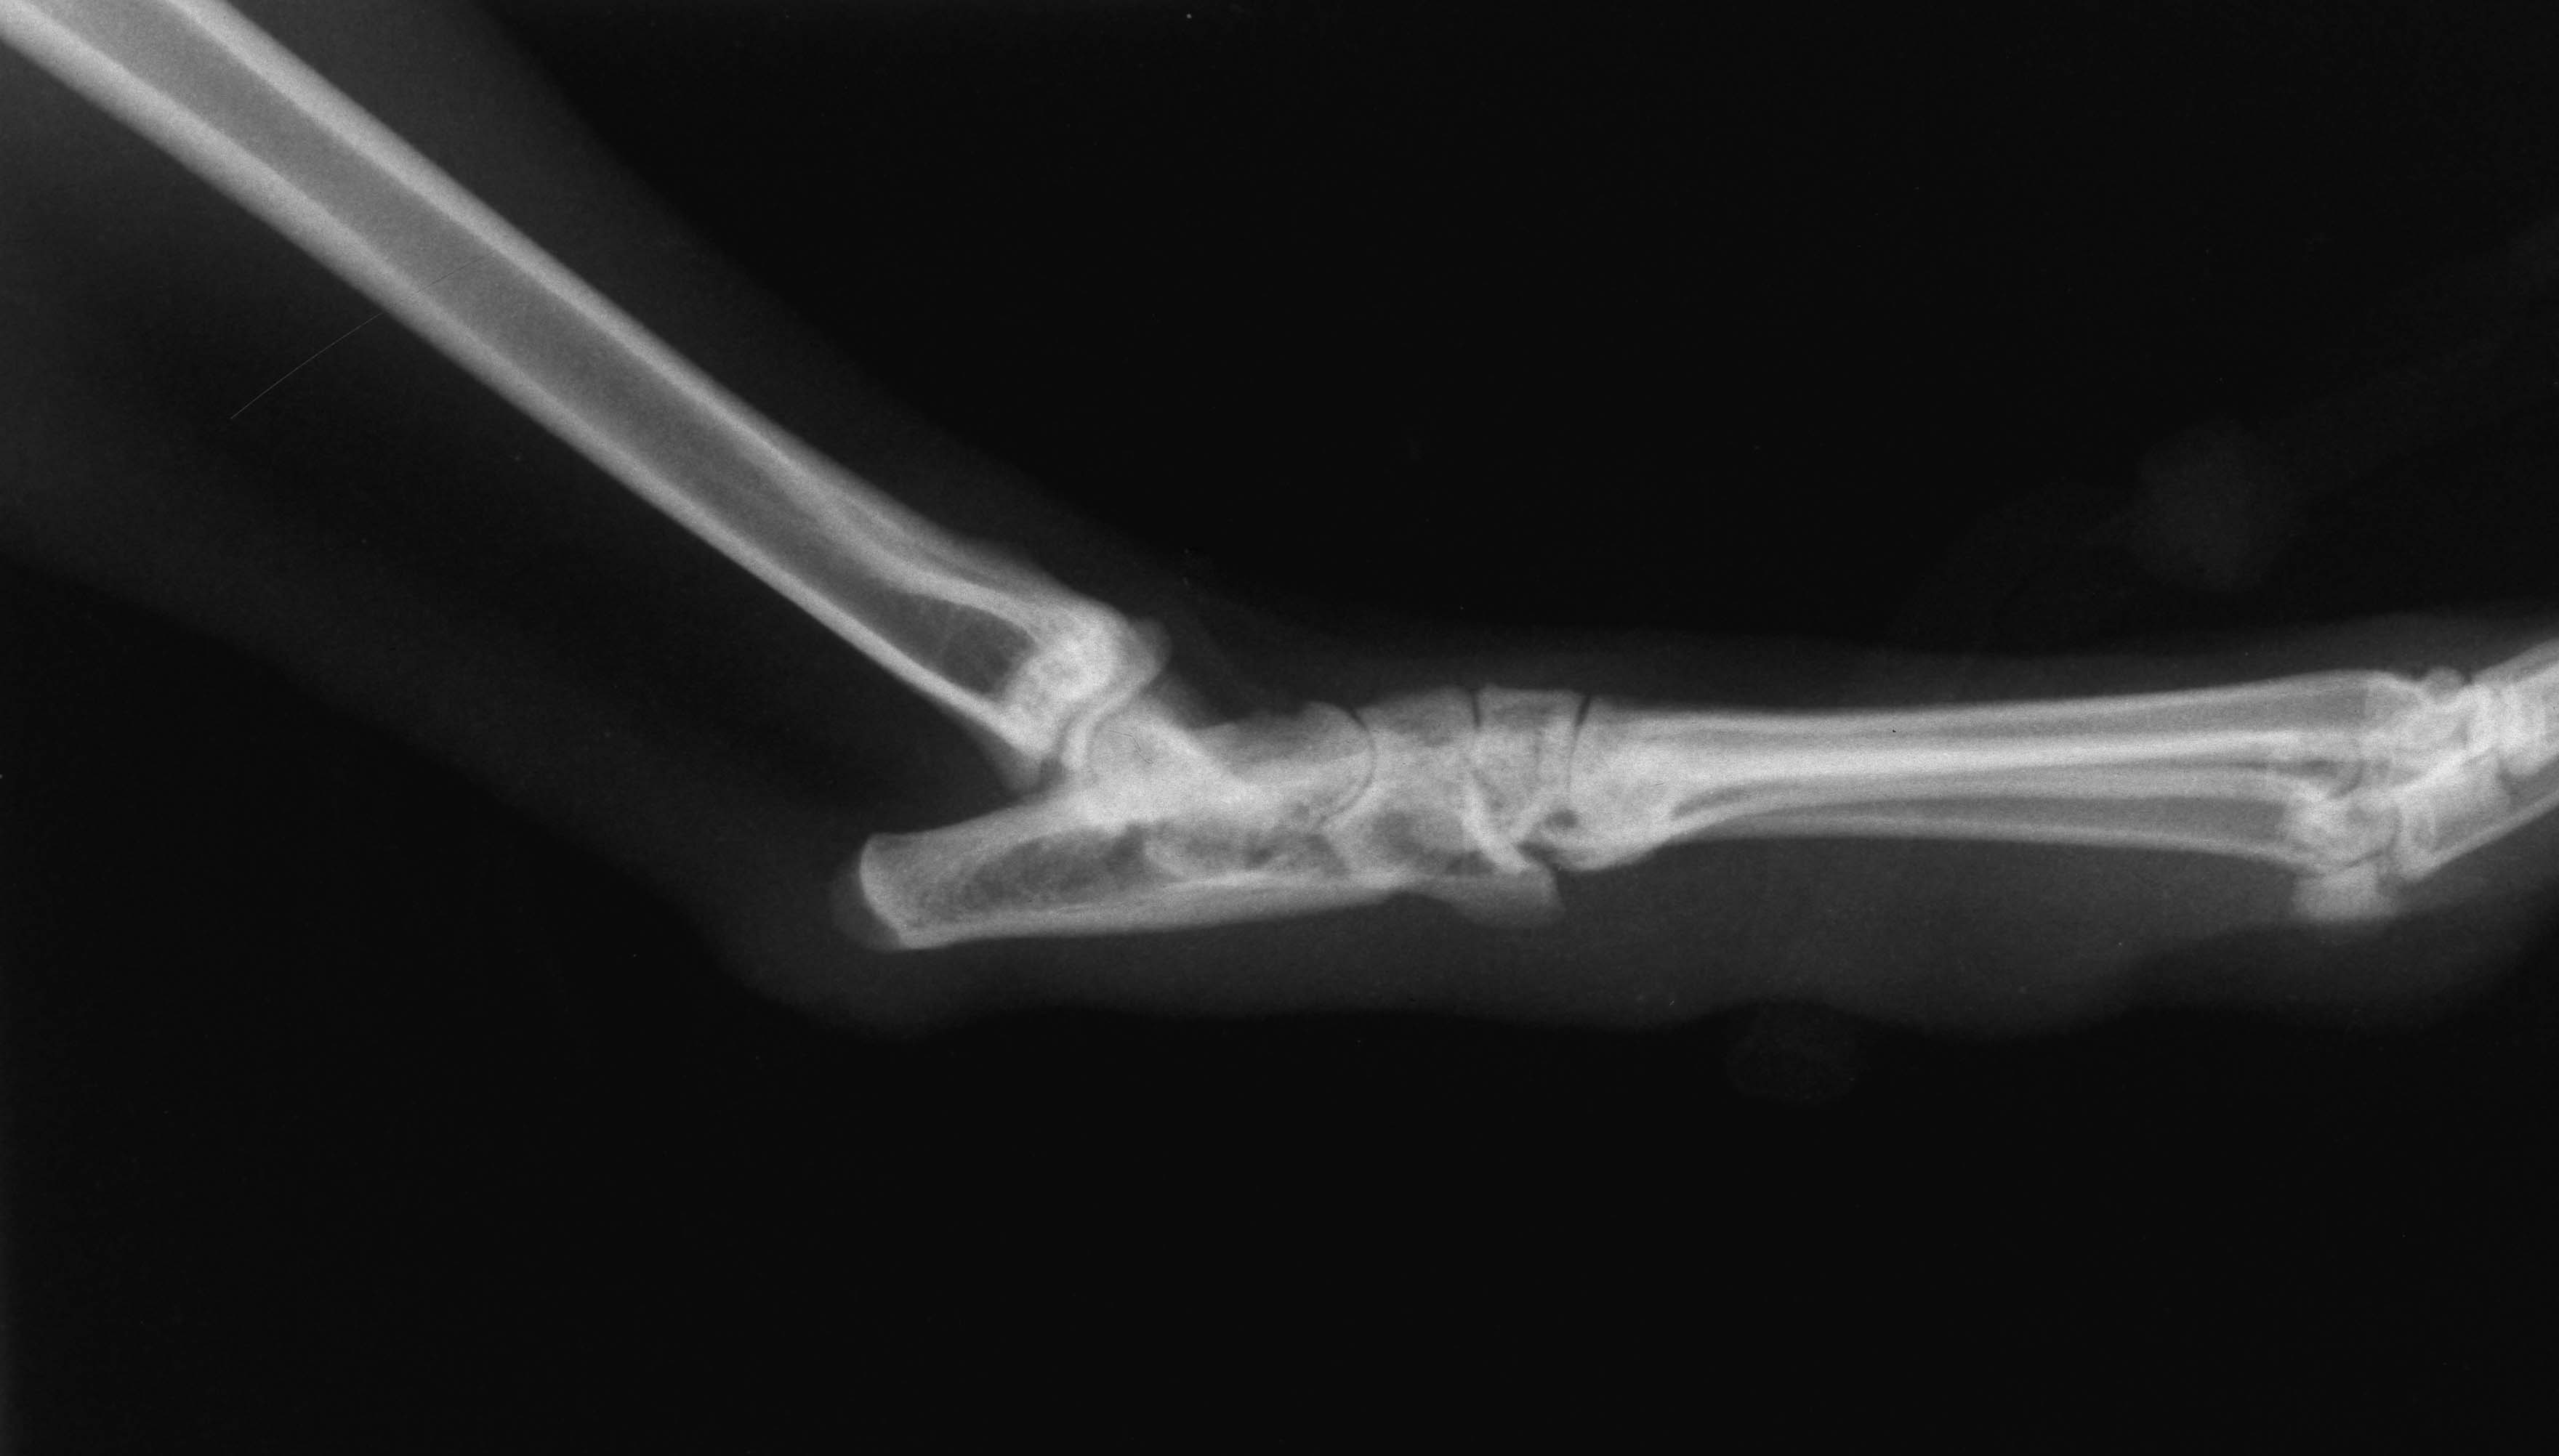

Normal hock lateral

Orthopaedics